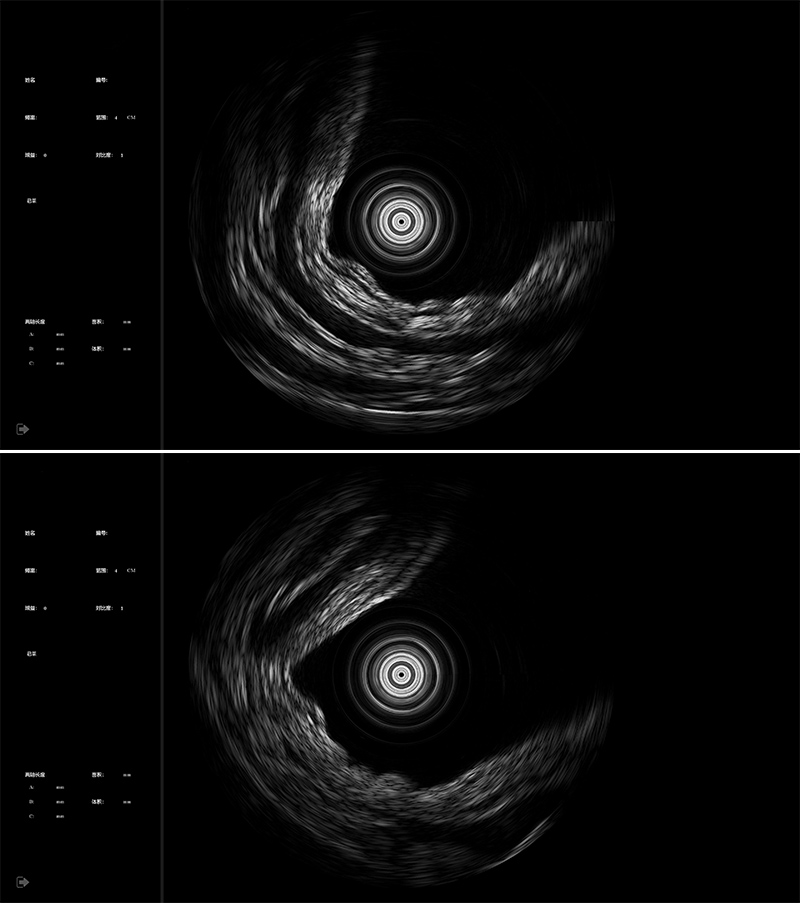

- 1200 rpm high-speed imaging

- 4K HD resolution

360°mechanical loop scan probe

- 2D mechanical ring scan /3D spiral scan is optional